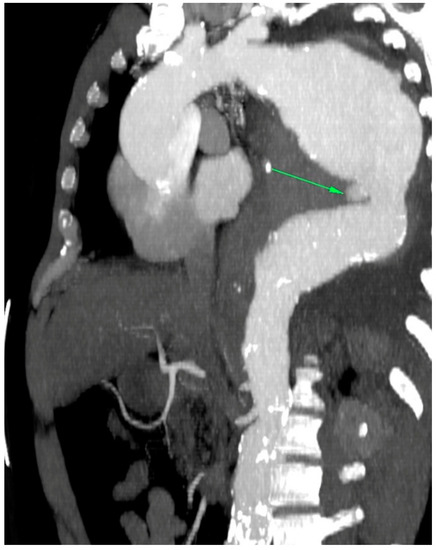

In the patients included in our analysis, there were three patients treated for an aortoesophageal fistula. Only one patient, treated for primary fistula with esophagectomy and TEVAR in the same procedure, survived (Figure 2, Figure 3, Figure 4 and Figure 5). This patient is still alive and in follow-up. The other two patients treated for a secondary fistula due to anastomotic leak after esophagectomy for esophageal cancer died after TEVAR. The incidence of an aortoesophageal fistula after TEVAR for primary aortic pathologies is low, as demonstrated in the European Registry of Endovascular Aortic Repair Complications (1.5%). In this cohort, the highest 1-year survival (46%) could be achieved via an aggressive treatment, including radical esophagectomy and aortic graft replacement [41]. In our patient population, we did not treat patients with a secondary fistula after TEVAR. In a 2014 review, 55 articles were included which reported on 72 patients treated with TEVAR for aortoesophageal fistula. Similar to our data (100% technical success rate), the technical success rate was 87.3%. Nevertheless, the overall 30-day mortality was significantly lower (19.4%) than in our series [42]. In a 2009 meta-analysis, 43 patients with aortoesophageal fistula were identified. Mortality after TEVAR was 19%. Patients who underwent esophageal surgery in the first month after TEVAR had lower fistula-related mortality during 6 months of follow-up compared to the other patients (p = 0.018) [43].

Figure 5.

Postoperative CT scan after TEVAR.